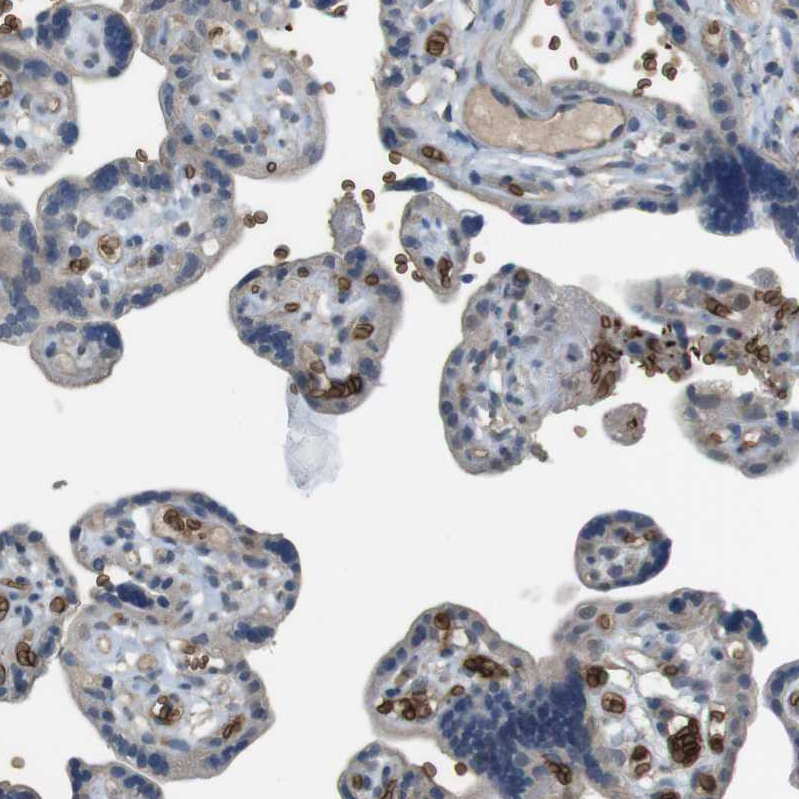

Immunohistochemical staining of human placenta shows moderate membranous positivity in erythrocytes.